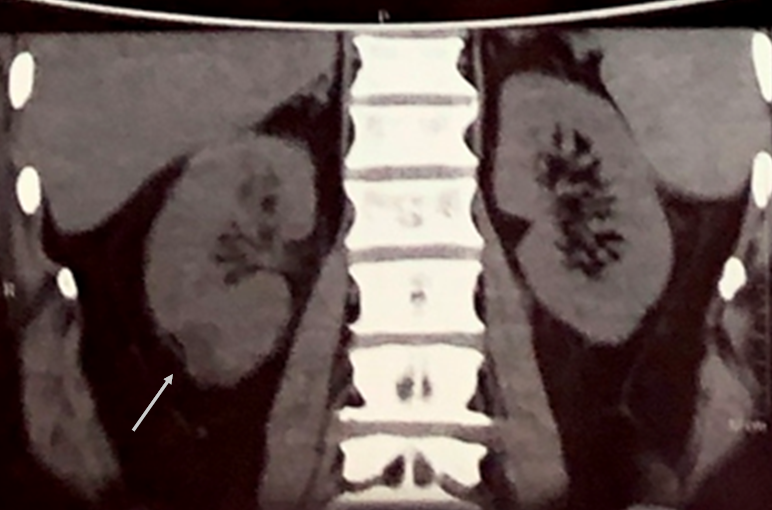

A 55-year-old poorly controlled diabetic male patient presented to our hospital with a history of high grade fever, pain in right flank radiating to back associated with burning micturition for 3 days. He was a known diabetic for 1 year and was taking oral hypoglycemic drugs. On admission, pulse rate was 110/min, blood pressure was 100/80 mmHg, respiratory rate was 20 per min and temperature was 39°C. His ophthalmic, cardiovascular system, respiratory system and central nervous system examination were within normal limits. His abdominal examination revealed tenderness over right renal angle. Blood sugar fasting was 294 mg% and HbA1c was 9.7%. Urine examination revealed no albumin or sugar, pus cells were present on microscopy. Renal function test showed blood urea – 114 mg/dl, serum creatinine – 2.85 mg%, sodium – 132 mEq/L, potassium – 3.9 mEq/L. Urine culture showed no growth. Blood culture showed growth of E. coli. Non-contrast computerized tomography (NCCT – abdomen) showed fuzzy cortical margins with perinephric fat stranding and focal hypodense area of 2.3 cm diameter in the cortex of the lower pole of the right kidney suggestive of pyelonephritis (Figure 1 [Fig. 1] and Figure 2 [Fig. 2]). No evidence of renal calculi or hydronephrosis was noted. The diagnosis of acute pyelonephritis with E. coli septicemia was made and the patient was treated with intravenous vancomycin, amikacin and tazobactam. He had an episode of confusion with worsening of his renal parameters. His serum urea increased to 220 mg/dl and creatinine increased to 3.5 mg%. Hyperkalemia was noted (potassium – 6.1 mEq/l). Acute kidney injury was suspected and managed conservatively. After 3–4 days, the patient improved significantly and he became afebrile.

Figure 1: NCCT abdomen showing fuzzy cortical margins with perinephric fat stranding suggestive of pyelonephritis

Figure 2: NCCT abdomen showing irregular hypodense area seen in the cortex of lower pole of right kidney